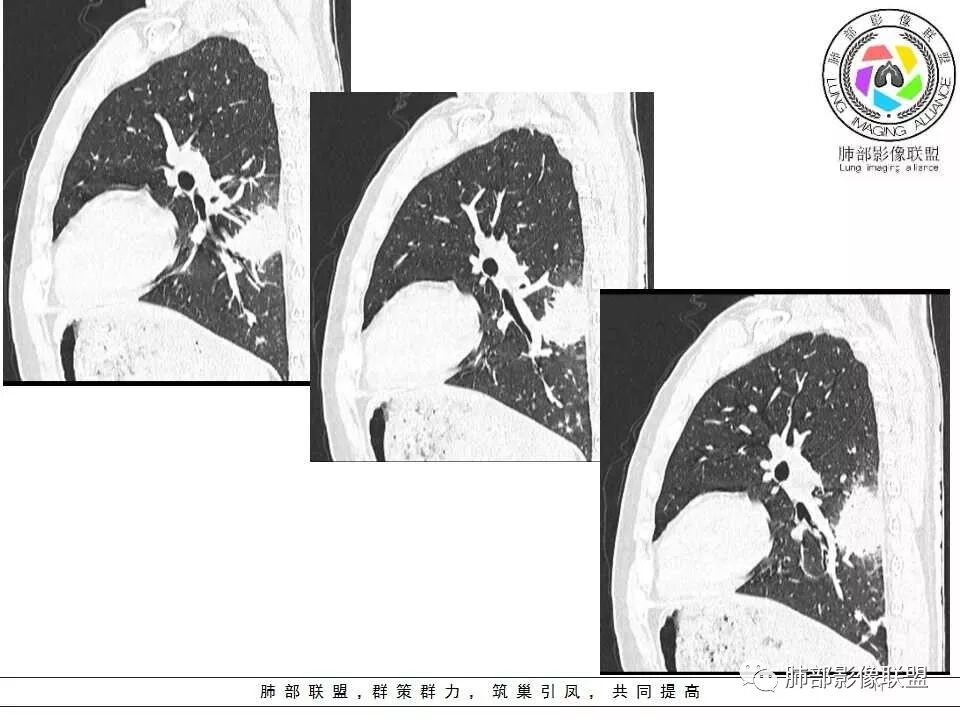

影像资料

青年男性,咳嗽、左侧胸痛10余天。血常规(一)。左下肺胸膜下见一肿块影,糊墙,长轴与胸膜平行(碰到胸膜往两侧走),近端支气管进入后堵塞,内有小片状低密度区,边缘见模糊的GGO。肿块周围见类似密度的小结节。综上考虑良性病变,隐球菌可能性大。

青年男性,左肺下叶实变影,长轴与胸膜平行,支气管进入后堵塞,边缘晕征,略膨隆,内有低密度影。结合病史,咳嗽,咳痰。考虑:炎性肉芽肿,隐球菌感染。建议检查隐球菌抗原、增强或穿刺活检。鉴别,淋巴瘤,肺链。

左肺下叶胸膜下肿块,密度不均,内见低密度坏死区,病灶边缘有膨隆,也有收缩,周围有晕,支气管进入近端阻塞,远端支气管走行通畅,病灶长轴平行胸膜,胸膜糊墙,周围可见多发类似结节,形态单一,考虑感染性病变,隐球菌?

青年男性,咳嗽,胸痛10天,白细胞不高,中性粒细胞不高,1月前有发热史,1年内体重下降10公斤,胸部CT所见左肺下叶跨背段及后基底段不规则形团块影,宽基底与胸膜相连,胸膜下脂肪间隙清楚(糊墙),长轴平行胸膜,内有坏死,边缘毛糙,周围见晕征,病灶旁有斑点状及小结节状影,病灶由外向内包绕支气管,考虑:炎性肉芽肿,隐球菌可能,结核待排,查隐球菌荚膜实验,必要时痰检及结核相关检查。

男性,29岁。咳嗽伴左侧胸痛10余天,吸气时胸痛加重,无发热/咳血盗汗。左肺下叶背段斑片样阴影,部分边缘欠清,周围可见小片状偏高密度影,近胸膜面分布。支气管进入病灶内,感觉走形较柔软,主体病灶长轴与支气管垂直,壁层胸膜下脂肪间隙可见,病灶内似可见更低密度影。结合临床,考虑炎性病变,隐球可能性大,结核抗体弱阳性,还是要待排的。

4、欺软怕硬:隐球菌不容易侵犯胸膜,病变发展到胸膜下之后,就开始向肺内发展,容易朝周边侵犯,向两侧发展,早期磨玻璃影的时候,支气管通畅,发展到密实的时候,堵塞支气管的中近端,不堵塞支气管的开口处。

在遥远的边远山区(胸膜下),有一群兄弟(多个性质相同的病灶),他们表面看起来很脏(有晕),但内心很实诚(基本不坏死),他们很聪明(踫到南墙也就是胸壁会往两侧走,往往会留点空气给自己→近端支气管进入堵塞或支气管可以直达病灶远端),兄弟们比较死心眼,就朝周围蔓延发展,不走其他路(少或无血道、淋巴道、支气管播散),比较自私,家里干净(内部空洞干净、壁光滑),家外脏,周围晕。这是大片状、多发结节状隐球菌肺炎的特点,不适用于免疫力特低下的。

7、含气支气管征与密度、晕征的关系:支气管可以直达远端,也可以近端堵塞,堵塞处支气管正常或稍扩张,走形正常;密度密实程度越高晕征越少,含气支气管近端堵塞的几率越高;如果周围晕征明显,密度偏低,边界欠清晰,含气支气管会直达远端;